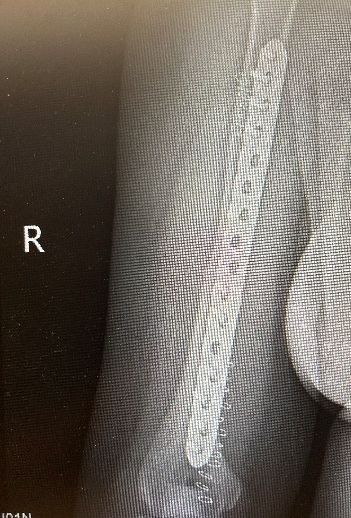

10月1日,李女士(化名)因车祸致右上肢骨折,13:30入院,黄磊医师团队完善各项检查后于18:00实行右肱骨骨折切开复位内固定术, 20:00安返病房。